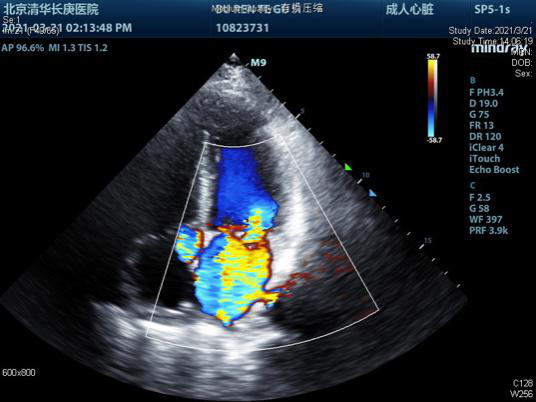

术前超声有二尖瓣大量反流 崔晓征(左一)与李温斌(右一)为患者手术

同样的故事,还发生在来自内蒙的老布仁特古斯身上。今年57岁的老布仁特古斯,因频繁出现活动后气喘,胸闷,被当地医院确诊为二尖瓣腱索断裂,出现大量反流,需尽快进行手术。为寻求更好的医治,一家人不远千里来到崔晓征的门诊。医生的直觉告诉他,情况紧急,老布仁特古斯不能再拖下去了,他一面安抚患者和家属,一面联系ICU为患者提供床位。住院仅两天后,崔晓征与李温斌为老布仁特古斯行二尖瓣成形手术,避免了瓣膜置换术后因长期抗凝导致出血等并发症。术后心脏超声显示,二尖瓣返流由术前的重度变成了微量,手术成功。